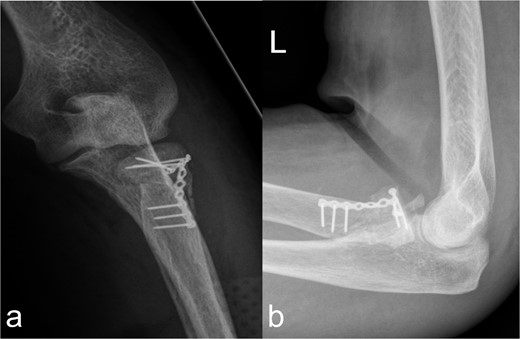

Treatment patterns of fractures of the caput and collum radii (2R1C3 and Mason stages II and III). (a, b) X-ray in two planes shows extensive coverage of the fracture fragments of the caput radii when the collum radii is straightened by the osteosynthesis material.